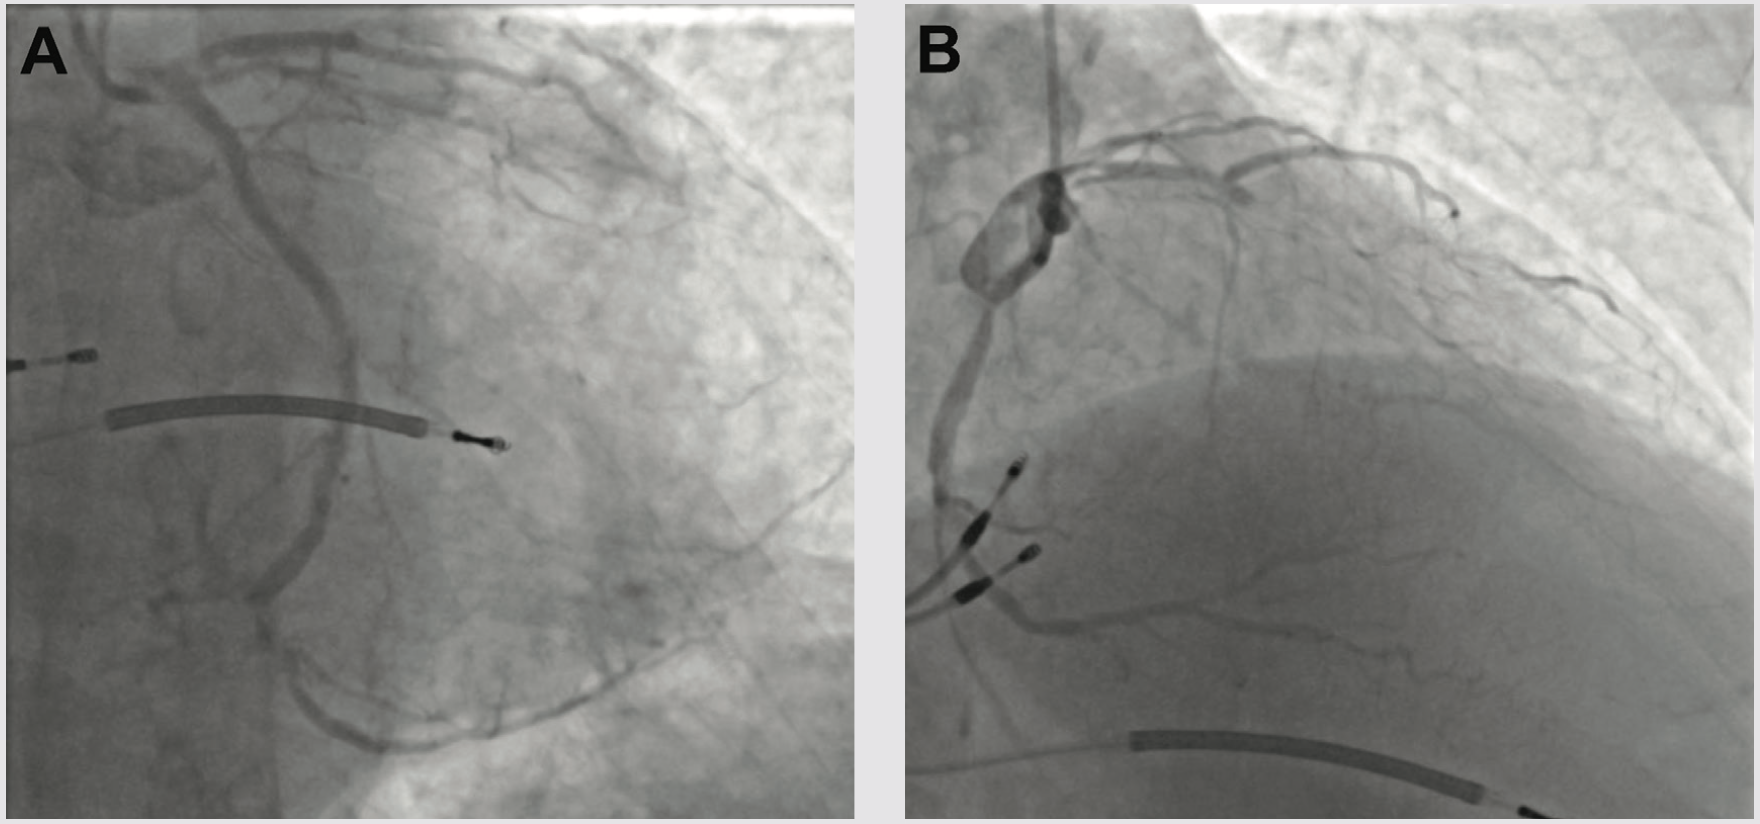

We next delivered the Impella CP and using single access guide technique (SHiP) through the Impella insertion sheath, placed a 7 French (Fr) left main guide, planning to treat the complex disease in the left circumflex. Diagnostic angiography demonstrated that the distal LCX to LPDA had progressed to a functional CTO. Using an antegrade wire escalation (AWE) strategy, we wired the LPDA with a Pilot 200 wire (Abbott Vascular), redirecting from a subintimal location to the artery true lumen. Predilation balloons would not expand, and intravascular ultrasound (IVUS) showed a severe arc of calcium and nodular calcium in the mid and distal LCX (Figure 3). With the assistance of a deep-seated guide extender, we treated with a 3.0 mm Shockwave balloon to modify the calcium compliance to facilitate optimal stent expansion (Figure 3). After Shockwave treatment, 1-to-1 sized AngioSculpt scoring balloons (Philips) expanded well, and we placed overlapping drug-eluting stents distal to the OM1 CTO into the LPDA. We next tackled the OM1 CTO with an AWE strategy. Using a Mongo wire (Asahi Intecc), we redirected from a subintimal location to the true lumen of the OM1. After 2.0 mm balloon inflation and nitroglycerine administration, the OM1 diameter was small, so we opted to stop at a balloon angioplasty result with non-flow limiting dissection, rather than placing a stent. We finally stented the proximal to mid left circumflex, IVUS optimized the stent expansion, and achieved an excellent IVUS and angiographic result (Figure 3). Having used 180 ccs of contrast to achieve the 2-vessel CTO AWE revascularization, we opted to stage the LAD CTO PCI procedure. We weaned the Impella in-lab, explanted the device, and the patient was discharged 3 days later at baseline renal function.

Three weeks later, we performed LAD CTO PCI. The LVEF had improved to 35%, and the patient was euvolemic and hemodynamically well compensated. Right radial occlusion and left radial vasospasm prevented 7 Fr radial access, so we re-accessed the LCFA, where angiography showed a widely patent iliac Shockwave treatment zone from the prior case. Using a 7 Fr system, diagnostic angiography demonstrated patency of the LCX, LPDA, and OM1 treatment sites. We next utilized an AWE strategy to address the LAD CTO (Figure 4). CTO wires immediately tracked subintimal and using a Mongo wire, we used mini-subintimal tracking and antegrade reentry (STAR) to reenter the LAD with <20 mm subintimal distance (Figure 4). Initial noncompliant balloons would not expand completely. IVUS showed (1) severe circumferential and nodular calcium in the proximal and mid LAD, and (2) limited (<20 mm) subintimal tracking before luminal reentry. We treated with a 3.5 mm Shockwave balloon to modify the calcium compliance to facilitate optimal stent expansion. After additional predilation with 1-to-1 sized noncompliant balloons, we placed overlapping stents, post dilated under IVUS guidance, and achieved excellent IVUS and angiographic results (Figure 4). The patient was discharged the following day, and on follow-up has had complete resolution of angina and no further heart failure exacerbations. Intravascular imaging identifies calcified stenoses that restrict stent expansion and reduce the durability of PCI revascularization. Shockwave intravascular lithotripsy improves the compliance of calcified stenoses to facilitate optimal expansion, with the goal of improving short- and long-term stent patency.